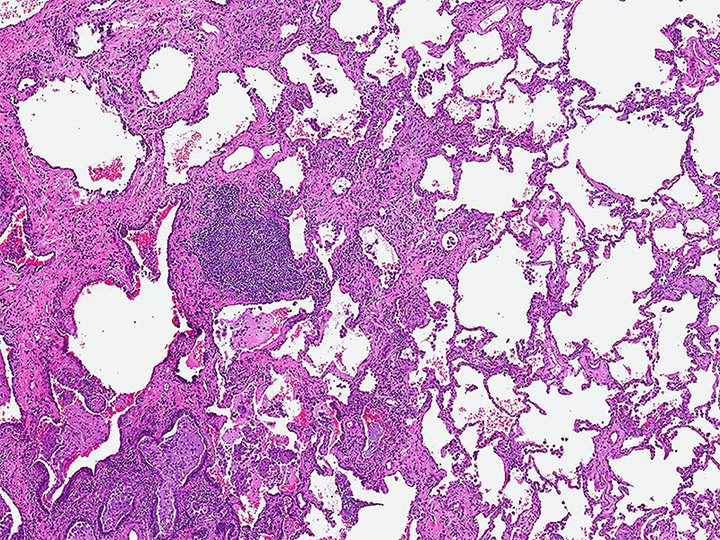

Low magnification photomicrograph illustrating prominent inflammation and airway-centered fibrosis in a patient with hypersensitivity pneumonitis.

Image courtesy of and used with permission from Kirk Jones, MD.